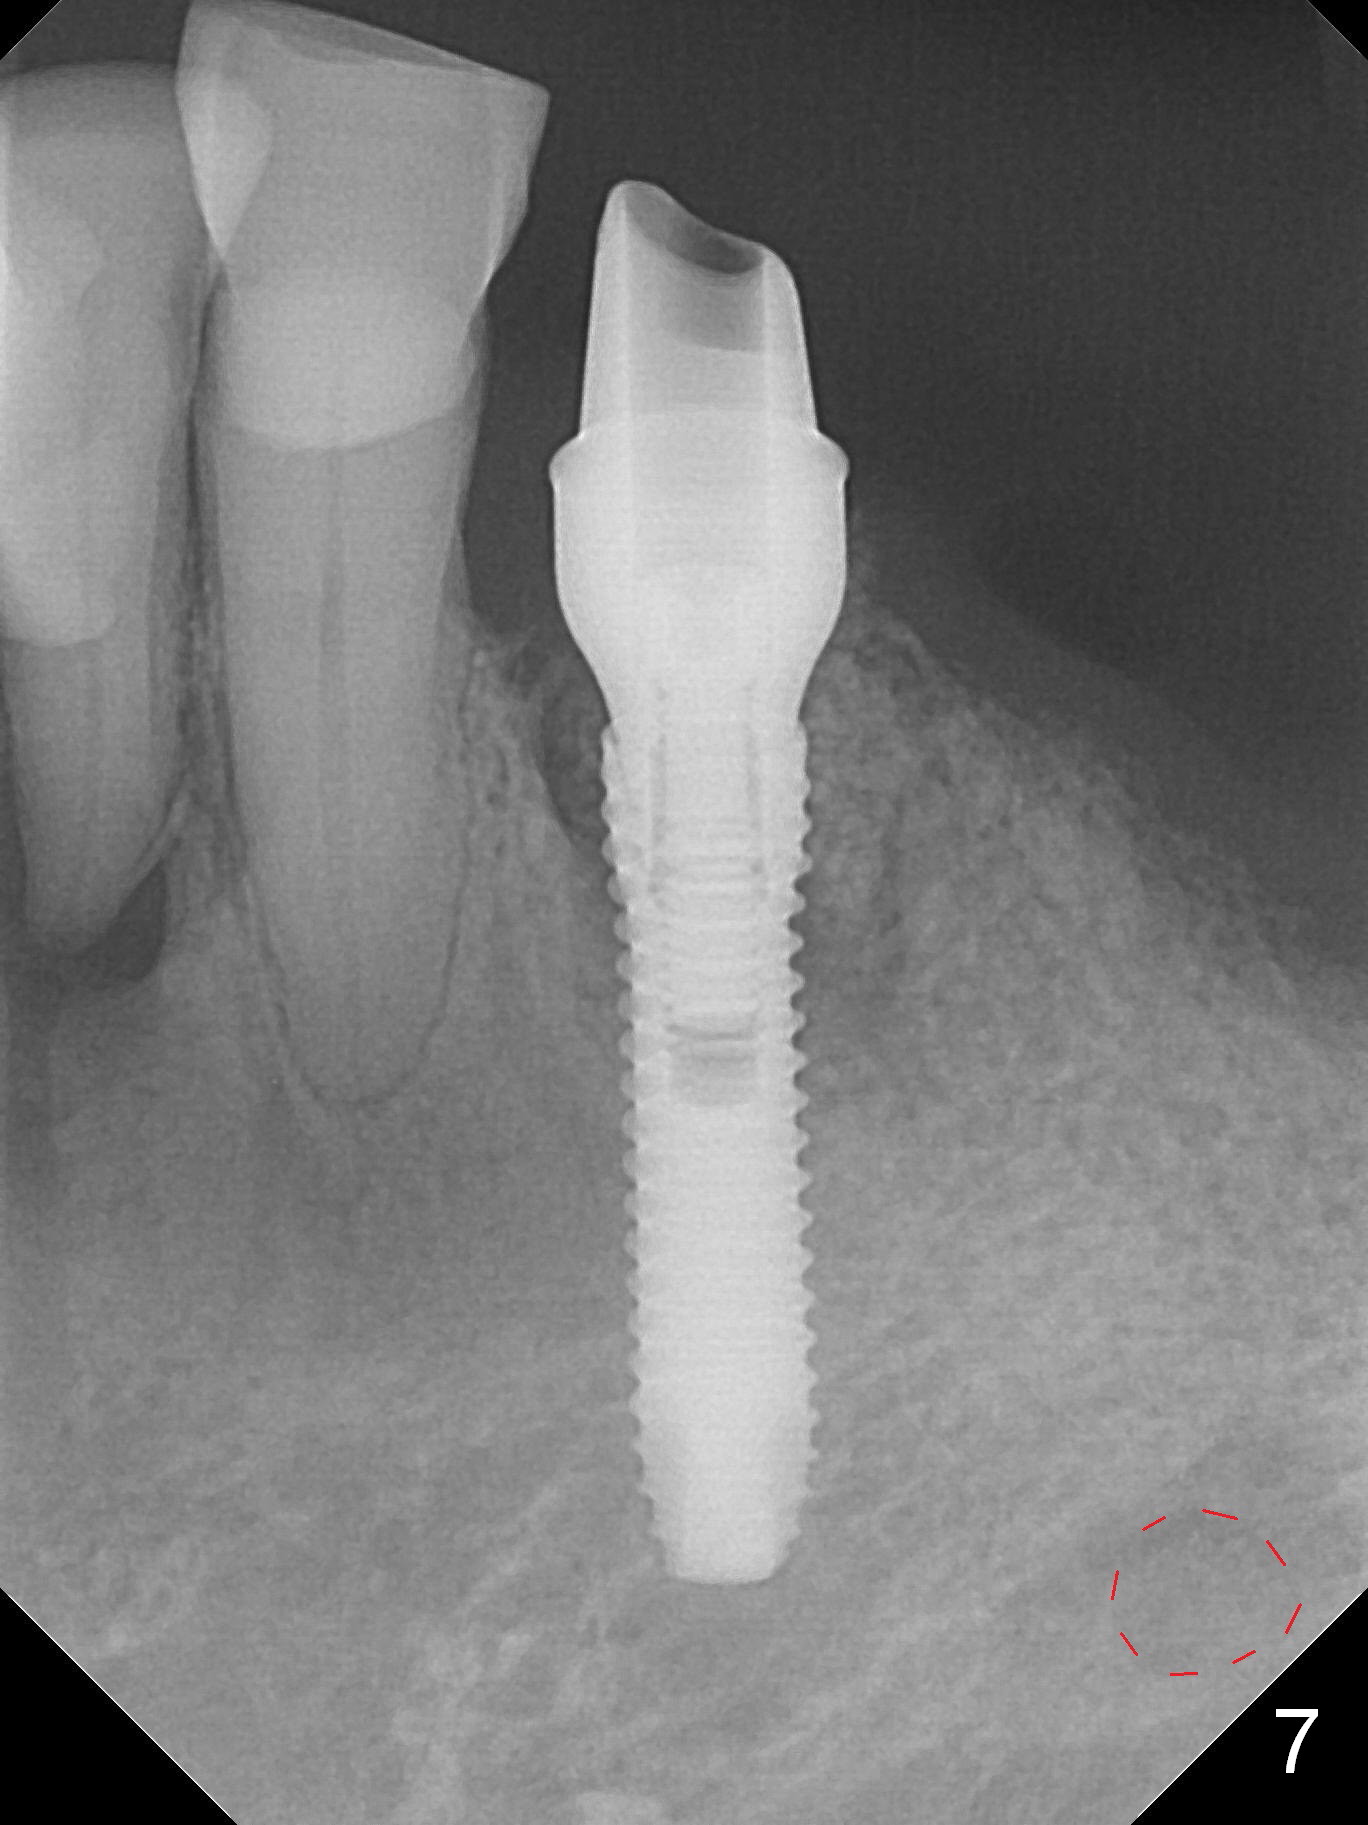

A 72-year-old man presents to clinic for implants because of pain associated with wearing the lower partial. The teeth #21, 24, 25 and 31 seem to be non-salvageable and are going to be replaced by implants so that the lower RPD can be reused (Fig.1). The edentulous ridge is atrophic (Fig.9 *). The upper complete denture appears to be functional. Since the tooth #21 is symptomatic (Fig.2) and the patient has chronic TMJ dislocation, the affected tooth is extracted first (Without antibiotic socket treatment) for immediate implant (Fig.3 (1.5 mm drill (placed more lingually)). The lower RPD is used as a surgical guide (Fig.4 (3 mm drill in place)). When a 3.8x16 mm implant is placed with bone graft (Fig.5 *), the underlying neurovascular bundle is undetected. A small field of panoramic X-ray is retaken; it seems that there is enough clearance from the Mental Foramen (Fig.2,6,7 (red dashed line)) and the Incisive Canal (pink dashed line). The implant is then placed 2 mm more apically (Fig.7) to reduce the chance of periimplantitis since the buccal plate is lost. A 5.5x5(5) mm abutment is placed (Fig.5) with more graft. The access of the abutment is left open so that a part of periodontal dressing is inserted for additional retention (Fig.8,9). The RPD is placed back for adaptation of the dressing. The patient is advised not to wear the RPD postop to reduce micromovement.

The patient returns 2 days postop because of hemorrhage (Fig.10,11 * after removal of loose periodontal dressing). Periodontal dressing is repacked (Fig.12). The hemorrhage may be due to incomplete removal of granulation tissue or invasion of the Incisive vessel intraoperatively, although there is no pain or paresthesia postop. Soft food is recommended without the upper complete denture. A provisional is fabricated (Fig.14 P) nearly 3 months postop (after changing the 5.5x5(5) mm abutment to 4.5x5(4) mm, Fig.13) when an implant is being place is #31.